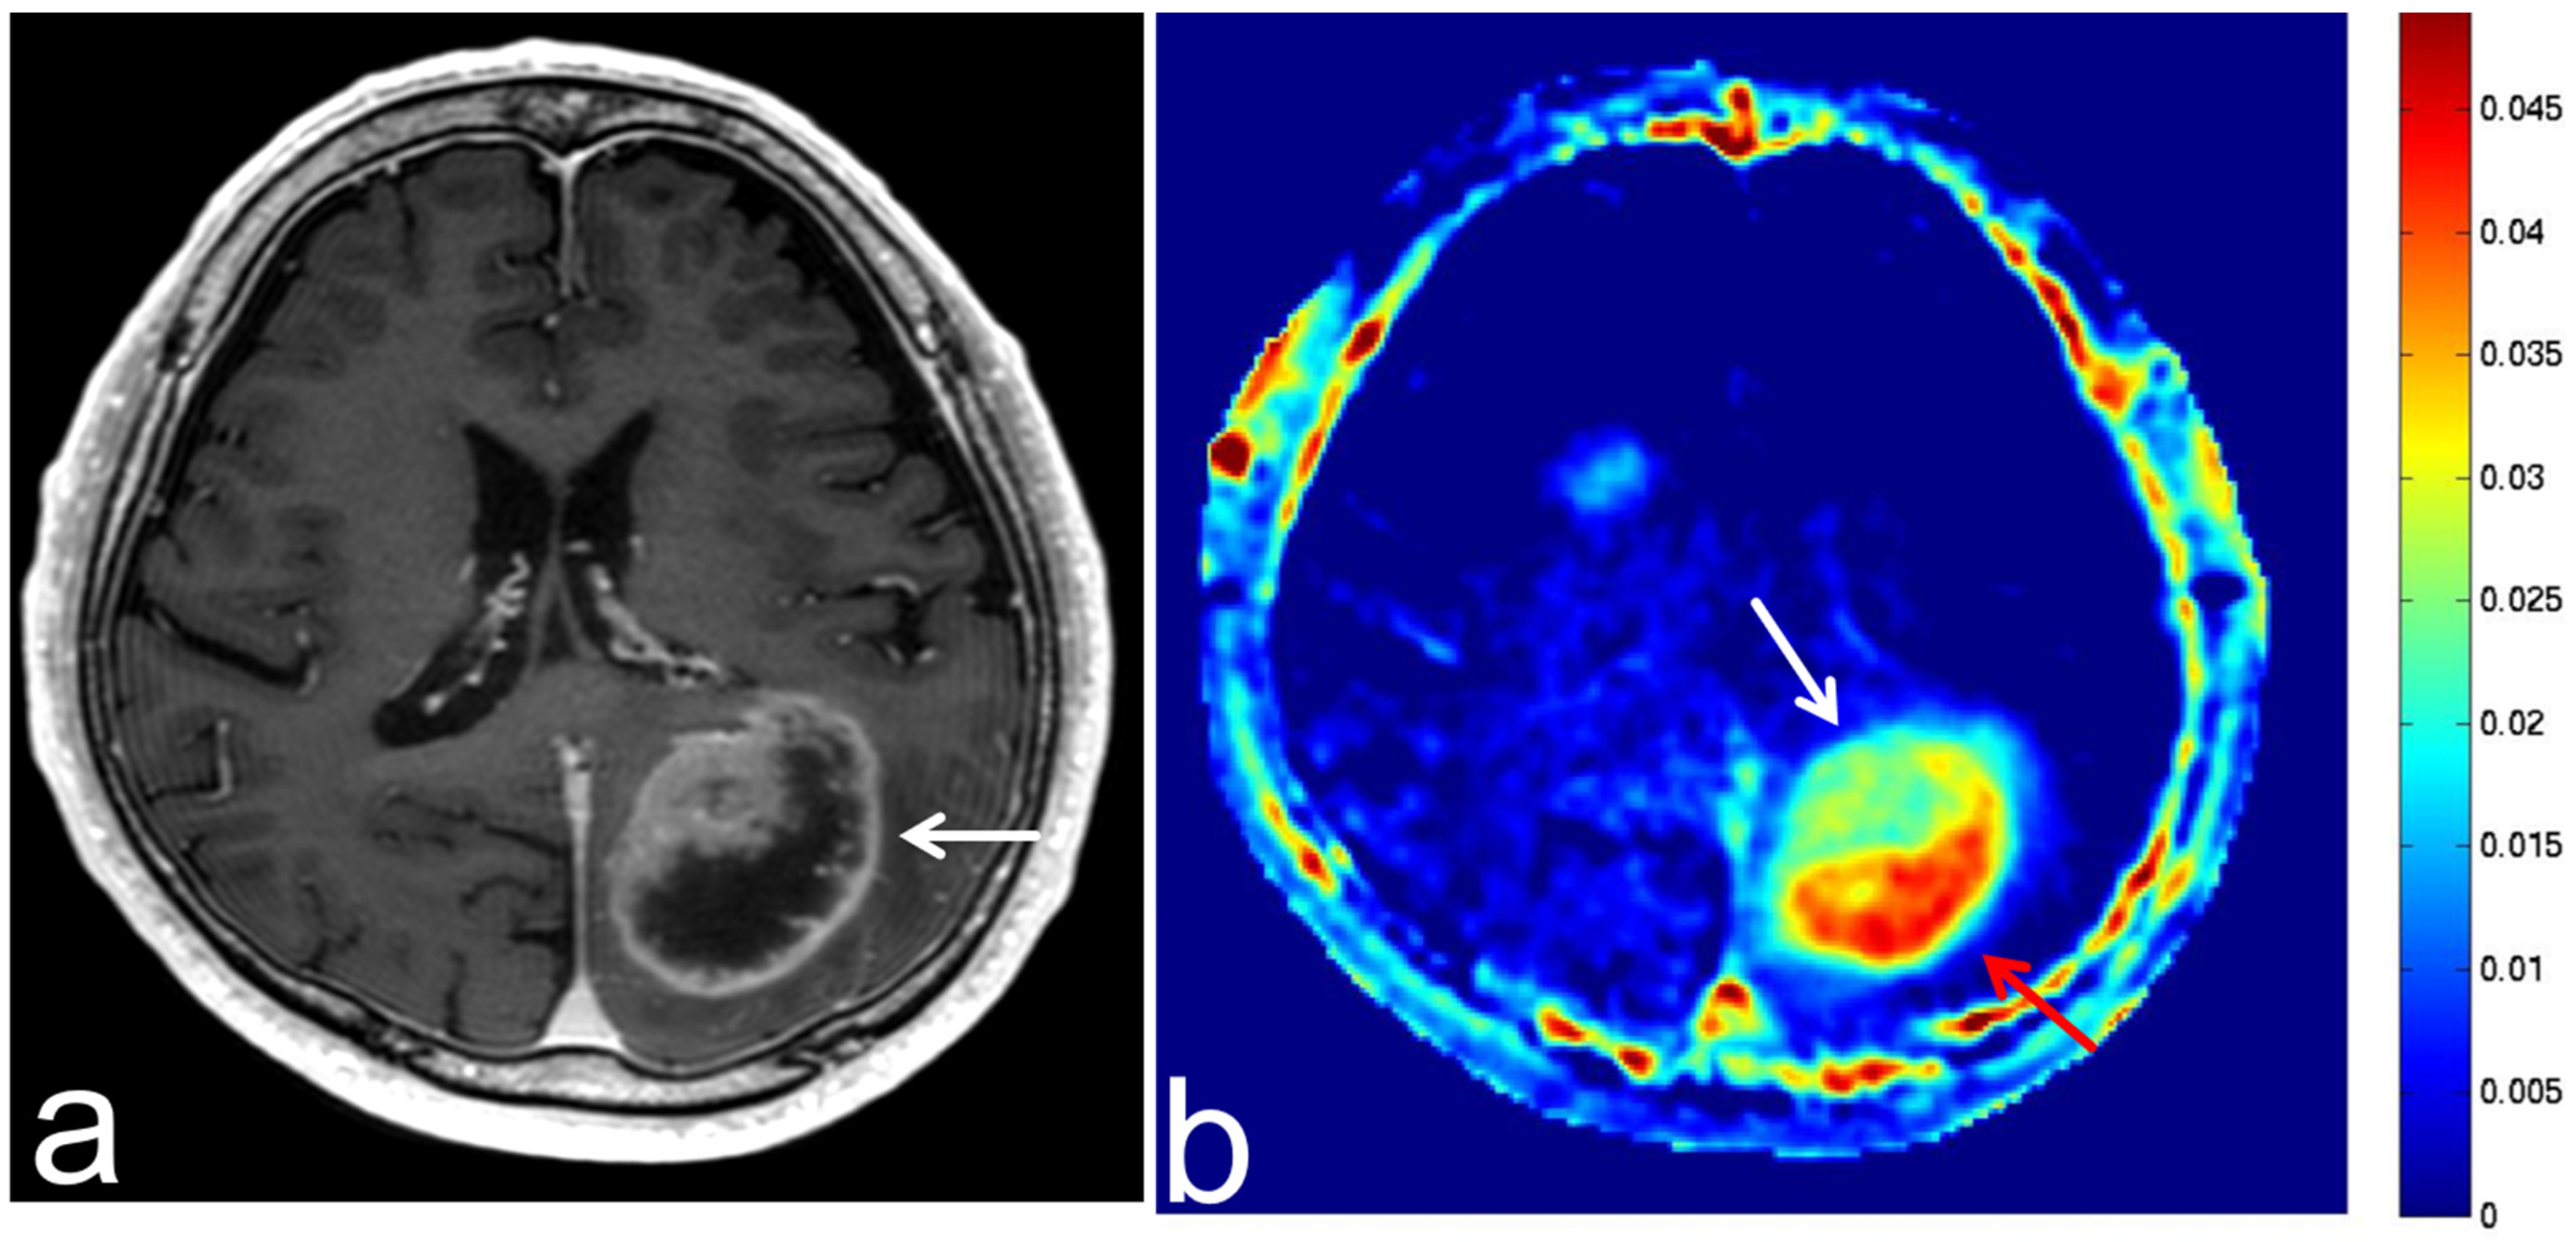

8.1. Radiation Necrosis

8.2. Leukoencephalopathy